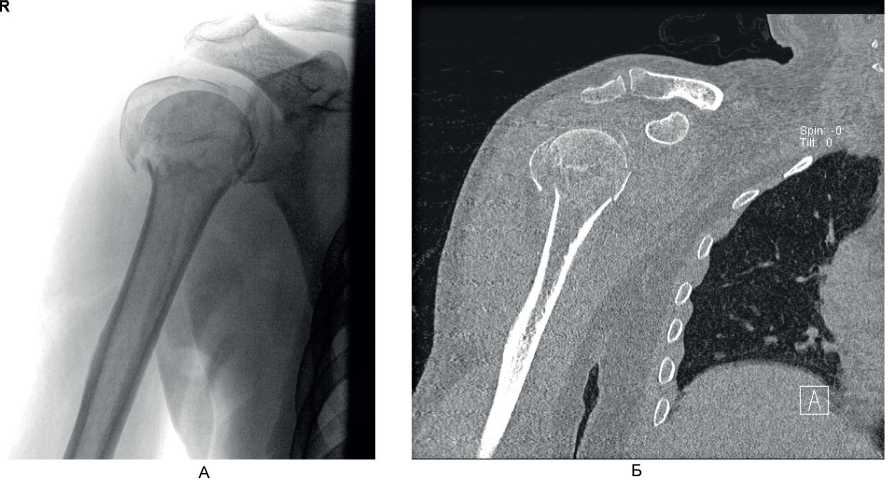

Клинический пример 2. Больной А., 50 лет, поступил в клинику ВЦЭРМ им. А.М. Никифорова в экстренном порядке. Выполнены рентгенография плечевого сустава в стандартных проекциях (рис. 8А), и компьютерная томография (см. рис. 8Б).

Рис. 8. Больной А., 50 лет. А – рентгенография плечевого сустава в стандартных проекциях; Б – компьютерная томография до операции

Перелом по классификации АО – С3.1. На 2-е сутки после поступления выполнено оперативное вмешательство – БИОС хирургической шейки правой плечевой кости. Рентгенография на 1-е сутки после операции представлена на рис. 9А, Б, контрольная рентгенография плечевого сустава через 6 мес после операции – на рис. 9В. Функциональный результат после операции – на рис. 10.

Рис. 9. Больной А., 50 лет. А, Б – рентгенография на 1-е сутки после операции; В – через 6 мес после операции

Рис. 10. Больной А., 50 лет. Функциональный результат через 6 мес после операции